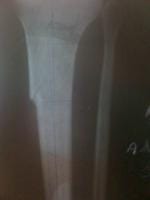

Fractura metafisiaria de tibia izquierda..

Doctor mi nombre es soy de la ciudad de Caracas Venezuela tengo 19 años de edad queria hacerle unas cuantas preguntas con respecto a mi fractura como lo indica el titulo una fractura metafisiaria de tibia izquierda el dia 01/01/09 ingrese al hospital y me indicaron que tenia que quedar internado hospitalizado durante 1 mes espere la operacion el dia 28/01/09 me operaron se me realizo una reduccion mas fijacion interna con placa lcp 4,5++ ingerto oseo en fisura de tibuia izquierda evolucione de forma satisfactoria y fui dado de alta el dia 30/01/09 acudi a control en el hospital pero devido a que me plantearon retiro de tornillo proximal, les plantie que necesitaba consultar con otros traumatologos y me indicaron que no era necesario devido a eso me retire del hospital y acudi a otro centro cree usted que sea el tipo de placa indicado el que me colocaron?.